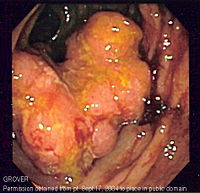

Endoscopy

A colonoscopy is the best test for making the diagnosis of Crohn's disease as it allows direct visualization of the colon and the terminal ileum, identifying the pattern of disease involvement. Occasionally, the colonoscope can travel past the terminal ileum but it varies from patient to patient. During the procedure, the gastroenterologist can also perform a biopsy, taking small samples of tissue for laboratory analysis which may help confirm a diagnosis. As 30% of Crohn's disease involves only the ileum, cannulation of the terminal ileum is required in making the diagnosis. Finding a patchy distribution of disease, with involvement of the colon or ileum but not the rectum, is suggestive of Crohn's disease, as are other endoscopic stigmata.The utility of capsule endoscopy for this, however, is still uncertain.